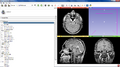

- We developed a scripted module for Slicer which can be used to connect to TCIA archive, browse the data, download and load into Slicer scene.

- The module is finalized and is ready to be published as a Slicer extension.